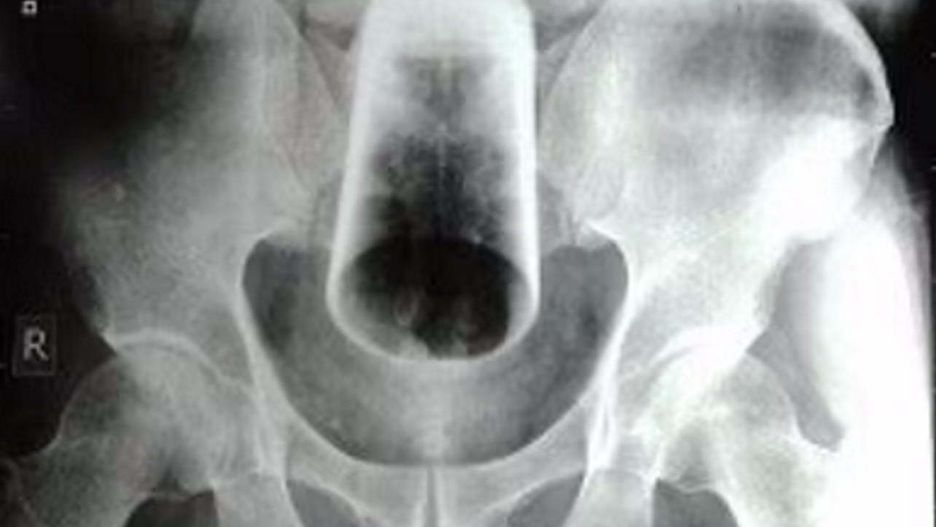

Mężczyzna trafił do szpitala z ciałem obcym w odbycieMężczyzna trafił do szpitala z ciałem obcym w odbycie

Źródło zdjęć: © "Journal of the Nepal Medical Association"

Lekarze byli w szoku, gdy okazało się, że pacjent miał w odbycie szklany przedmiot o długości 12 centymetrów. 47-latek próbował usunąć go samodzielnie, ale bezskutecznie.

Lekarze musieli zmierzyć się z trudnym zadaniem. Próby przeprowadzenia sigmoidoskopii, a także ręcznego usunięcia szklanego przedmiotu przez odbyt nie przyniosły rezultatu. Medycy odstąpili od obu procedur z uwagi na duże ryzyko pęknięcia szklanki, a co za tym idzie zagrożenia uszkodzeniem ściany jelita lub zwieracza odbytu. Wszystko dlatego, że "szklanka znajdowała się wysoko, była odwrócona i ciasno zaklinowana".